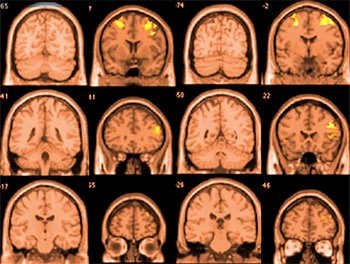

In this study, researchers focused on brain volume, which refers to the size of different brain regions. Brain volume is an important indicator of brain health. When certain areas become smaller, it can affect how a person thinks, feels, and behaves.

The results showed that people who regularly use cannabis tend to have a smaller amygdala. The amygdala is a part of the brain that plays a key role in emotions, especially fear and stress. Changes in this area may affect how people respond to emotional situations.

Tobacco use was linked to even wider changes in the brain. Smokers were found to have smaller volumes in several regions, including the amygdala, the insula, and the pallidum. The insula is important for self-awareness and emotional processing, while the pallidum is involved in movement and motivation.

The study also found that smokers experience a faster decline in gray matter over time. Gray matter is a major part of the brain that supports thinking, memory, and decision-making. Losing gray matter more quickly may increase the risk of cognitive problems later in life.

Another important finding came from genetic analysis. The researchers found that people who smoked more cigarettes each day were more likely to have a smaller hippocampus. This part of the brain is essential for memory and learning.